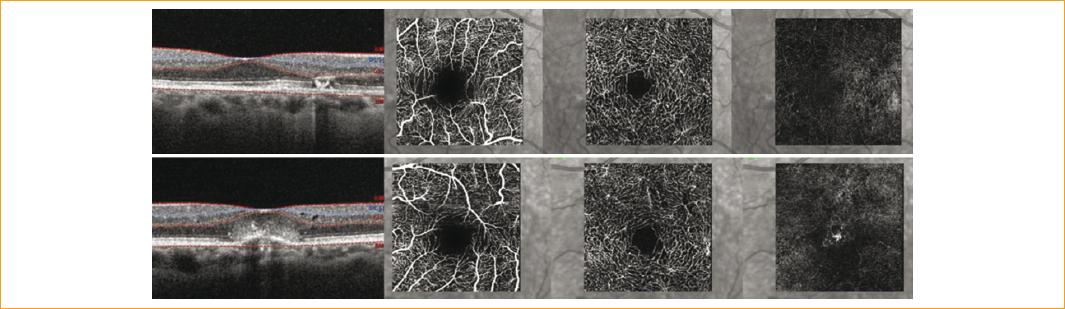

Figura 2 Imagen superior: angiografía por tomografía de coherencia óptica (OCT-A) del ojo derecho, plexo superficial con disminución de la densidad vascular leve, en el plexo profundo se observan vasos telangiectásicos perifoveales. Imagen inferior: OCT-A del ojo izquierdo, en el plexo superficial y profundo vasos telangiectásicos, pérdida de densidad vascular y en la capa avascular neovascularización.

El plexo vascular más afectado fue el profundo, en un 94%. En el 35% de los pacientes se logró visualizar vasos en ángulo recto (Fig. 3). Las características morfológicas que observamos en los vasos afectados fueron: un engrosamiento con dilataciones focales y, solo en el 33%, lesiones aneurismáticas con morfología (Fig. 3).